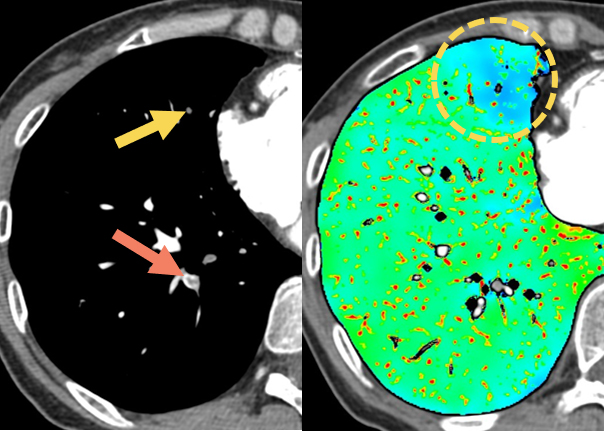

図3 PE疑いでのGSI撮影症例

PEが疑われた症例の造影検査。血栓がある(→)ことは間違いなかったが、後からヨード分布画像を作成。確認してみるとS5領域(〇)も血流が低下しており、血栓がある(→)ことが判明した症例。